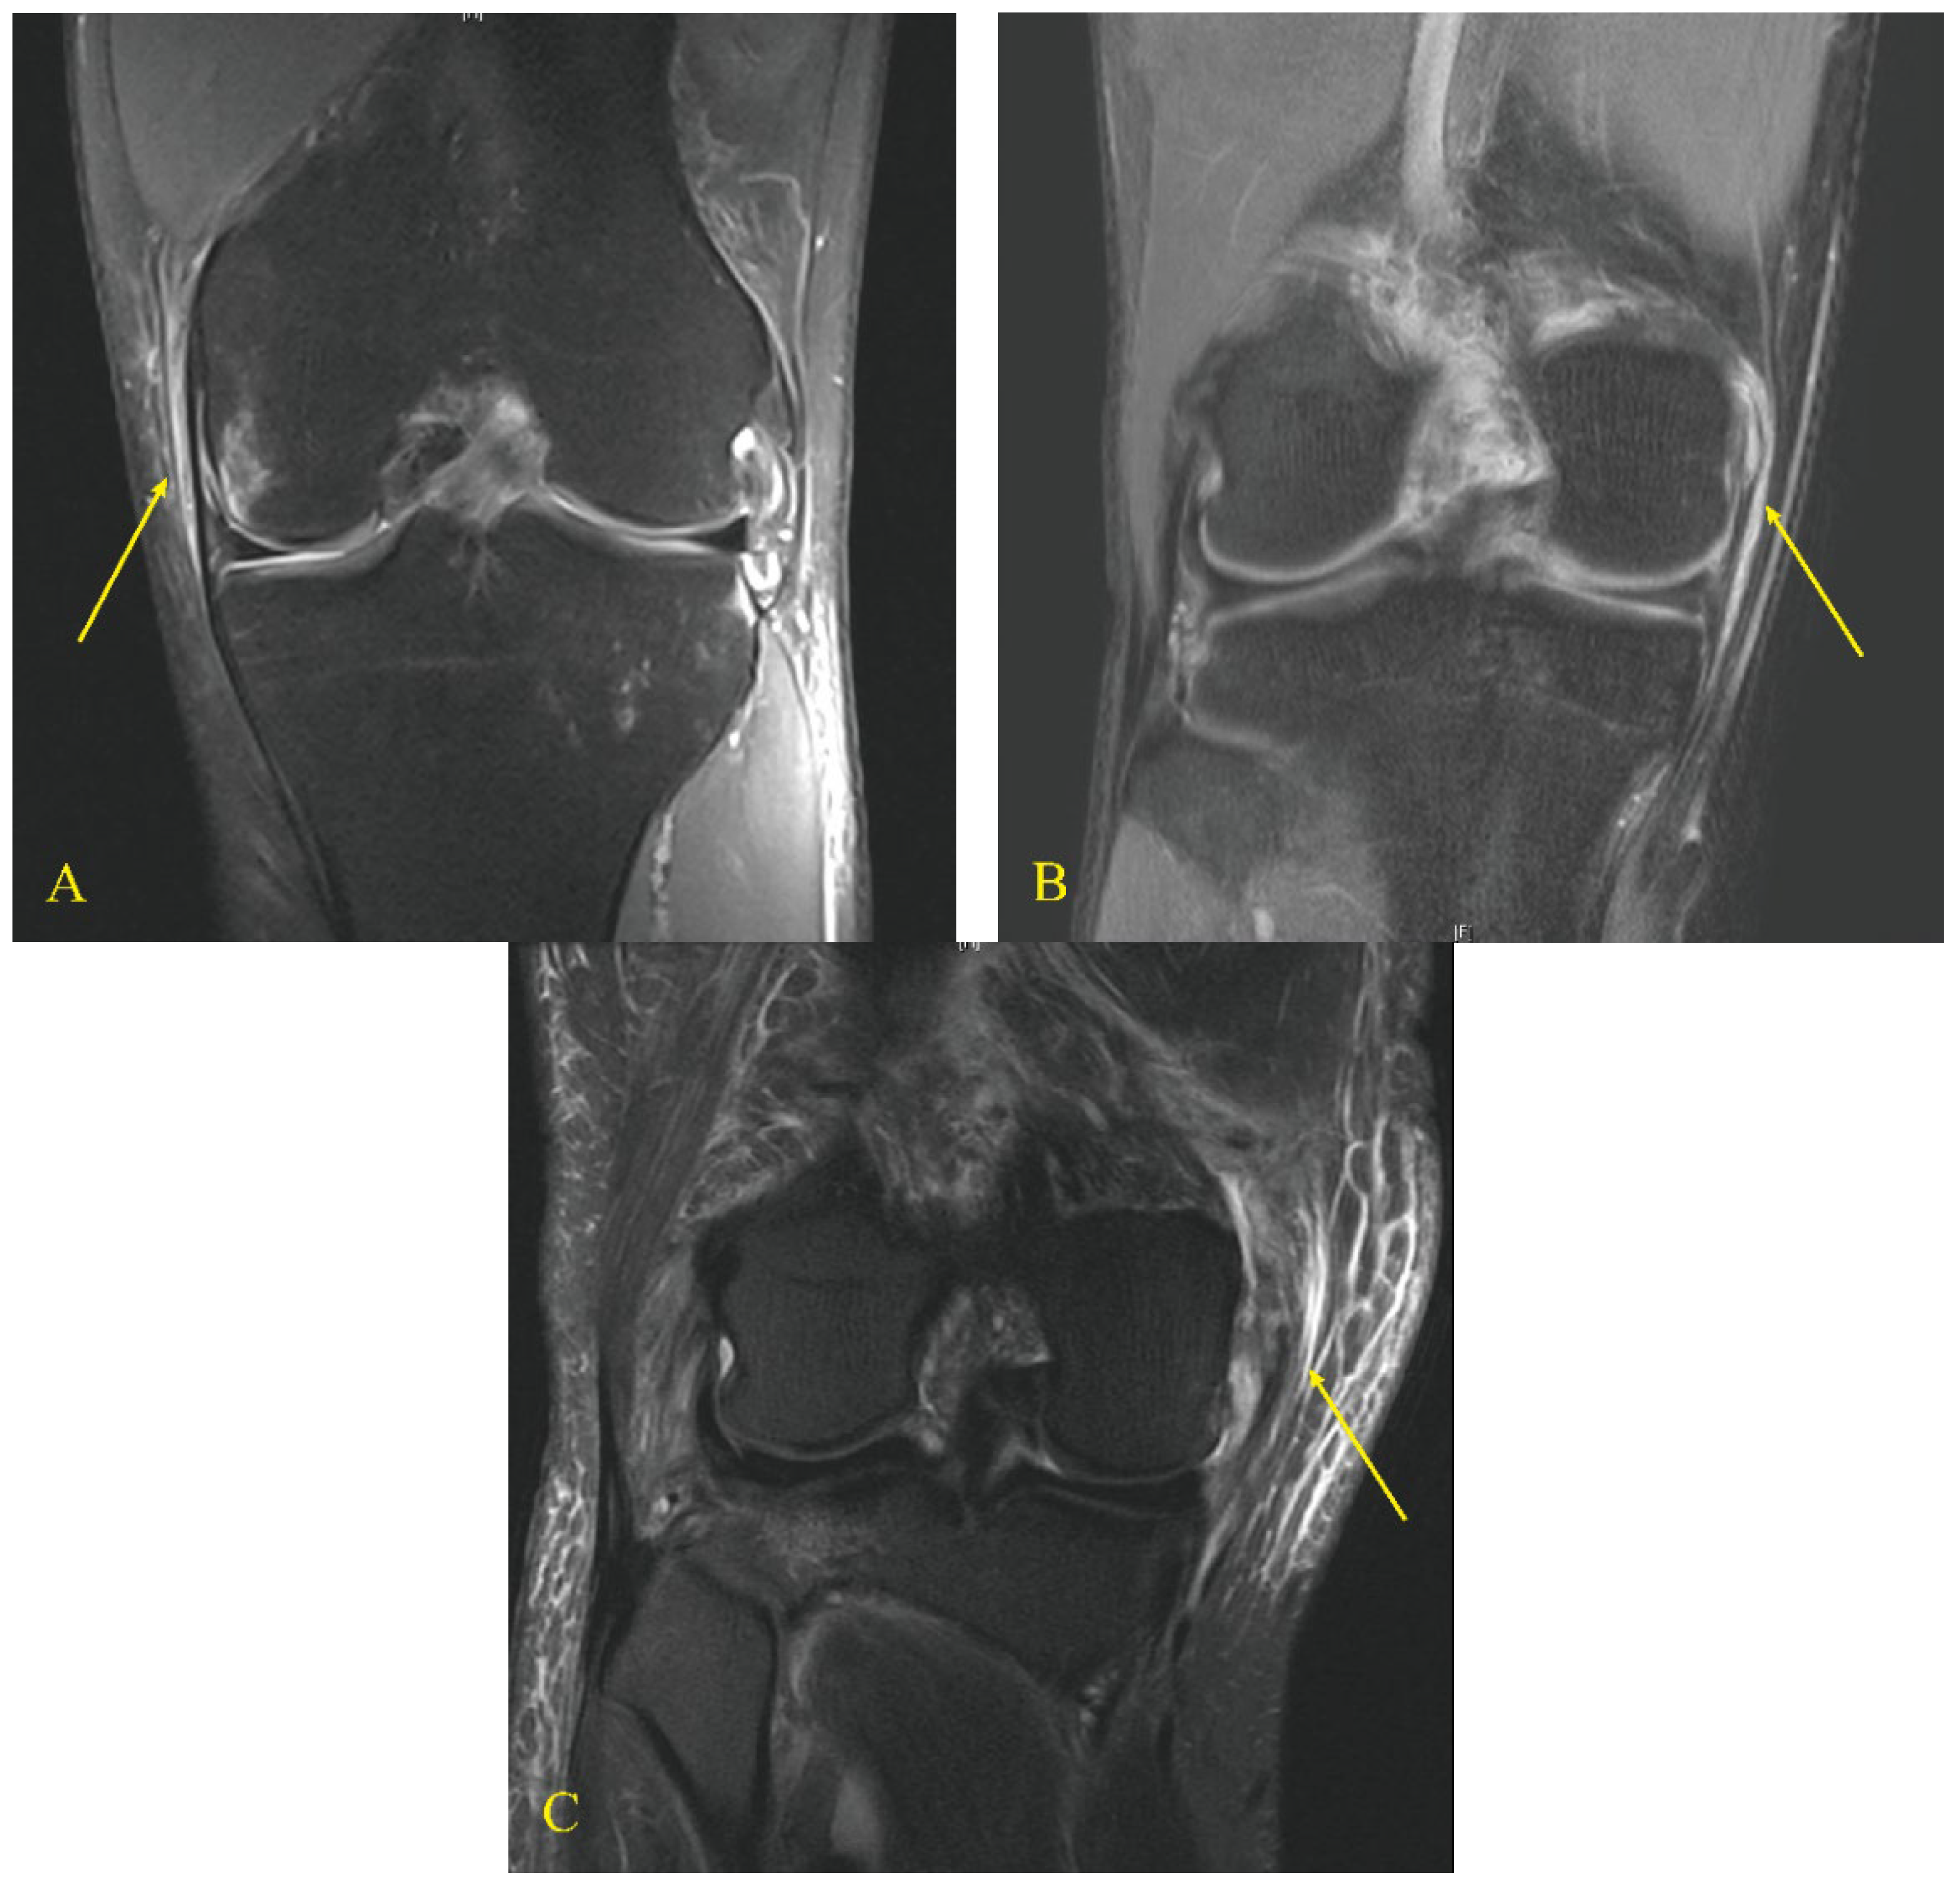

A total of 1187 patients underwent autologous ACL reconstruction during the study period. Of these, 169 patients were included in the study (Figure 1). As per the graft type used in ACL reconstruction, the patients were divided into two groups: group B, ACL reconstruction using a BPTB graft (n = 92) and group H, ACL reconstruction using quadrupled hamstring graft (n = 77). Each group was subclassified according to the grade of MCL injury on magnetic resonance imaging (MRI) scans [27]: grade I included peri-ligamentous edema around the MCL on fluid-sensitive sequences; grade II included partial disruption of the ligamentous structures; and grade III included complete disruption of the superficial and deep MCL (Figure 2) [27].

Figure 2. Grades of MCL injury on magnetic resonance imaging scans. Grade I (A) peri-ligamentous edema around the MCL on fluid-sensitive sequences, grade II (B) partial disruption of the ligamentous structures, and grade III (C) complete disruption of the superficial and deep MCL. Yellow arrows indicate the torn MCL based on the grade.